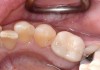

Fig 8. Loss of restoration and subsequent tissue overgrowth from broken abutment screw as shown in the radiograph (Fig 9).

Figure 8

Fig 9. Radiograph depicting fractured screw inside of the implant.

Figure 9

Fractured screws are challenging to retrieve, particularly when they are abutment screws. If the screw head is accessible, a hemostat can be used to remove it. However, when the screw breaks inside the implant (Figure 8 and Figure 9), removal can be highly complicated in order not to damage the implant’s internal threads. Therefore, many implant manufacturers have developed screw-retrieval kits. Because it is critical to be able to visualize the area, magnification using loupes and a surgical microscope may be necessary.8 Additional methods can be used to remove the fractured screw. A ¼ round bur set on a high speed can be used by lightly activating it, touching only the side of the screw. After repeating this technique several times, the screw may be able to be backed out with an explorer tip. Ultrasonic tips with copious irrigation may also dislodge the screw.7,20 In cases in which this fails, a small slot can be made in the head of the screw to back it out.21 If screw threads have been damaged during retrieval, they may be retapped using a tool obtained only from the implant manufacturer.7